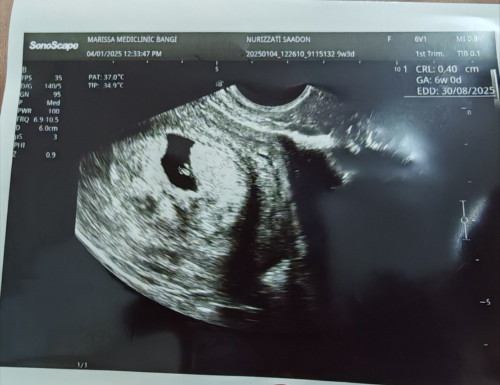

Sy klau ikut LMP 9w tp scan baru 6w

Last week sy scan baru 6w tp nmpk kedip2 jantung cuma bila doc nk try dgr bunyi heartbeat tak dpt dgr lg.. Doc takde la ckp ape2 cuma doc suruh doa byk2 je.. Pastu lepas 2 hari ade spotting urat darah mcmtu tp tak seharian, bila ade keputihan baru boleh nmpk brown2 tu keluar.. Ade tak sape2 ade pengalaman mcmni.. Sbb usia kandungan lari dari tarikh last period and start ade spotting.. Sy dh pernah 2 kali gugur.. Hati risau.. Sbb mcm same je sprti sebelum ni..